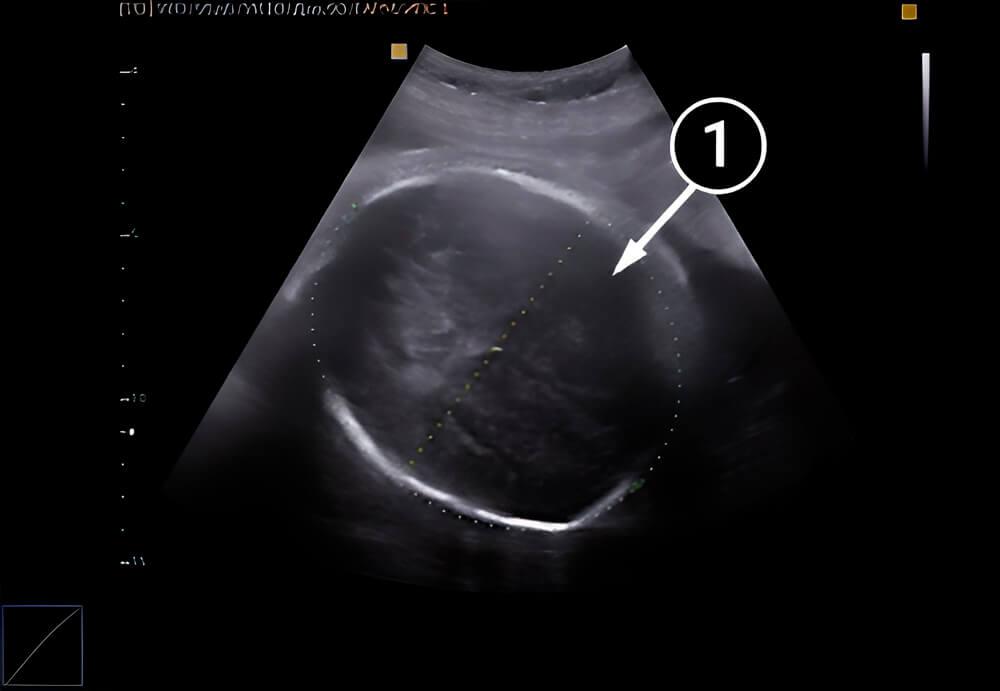

Lo que podemos ver en un ultrasonido

Aquí vemos la cabeza del bebé desde arriba. La línea de puntos indica su circunferencia y diámetro. Mide cerca de 96 mm.